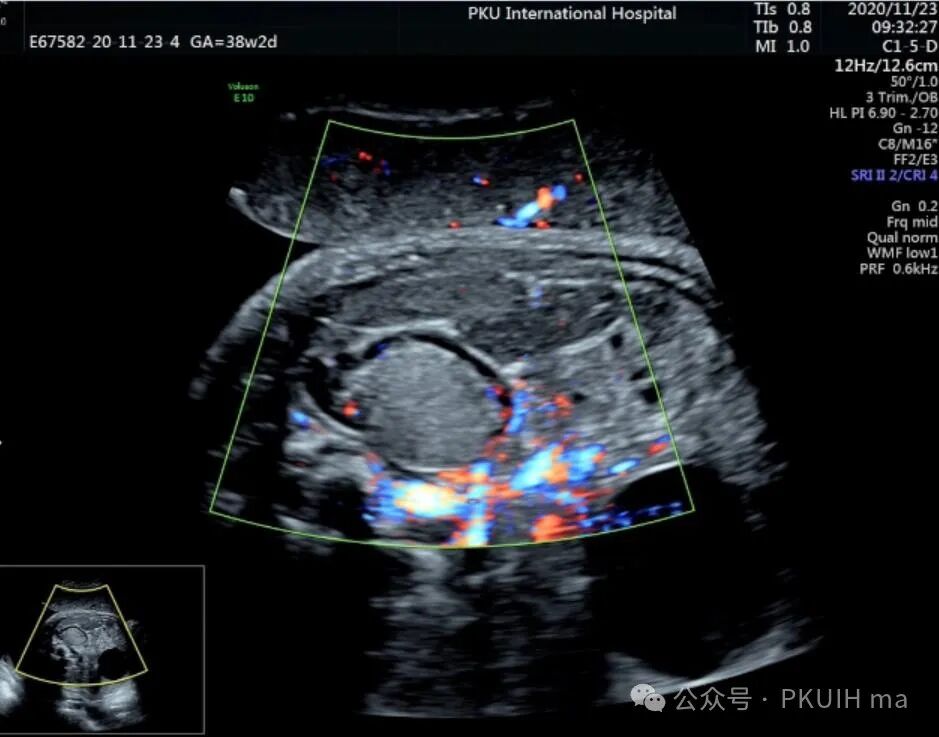

上图是一例在孕晚期发现的肾上腺占位,生后病理证实为神经母细胞瘤的患儿,生后及时做了治疗预后非常好,目前宝宝各项指标都很好。

同时在孕晚期也发现孕妇羊水增多

这几年我们在孕晚期发现有3例神经母细胞瘤胎儿,预后都很好。在孕晚期超声中建议常规扫查下胎儿双肾区